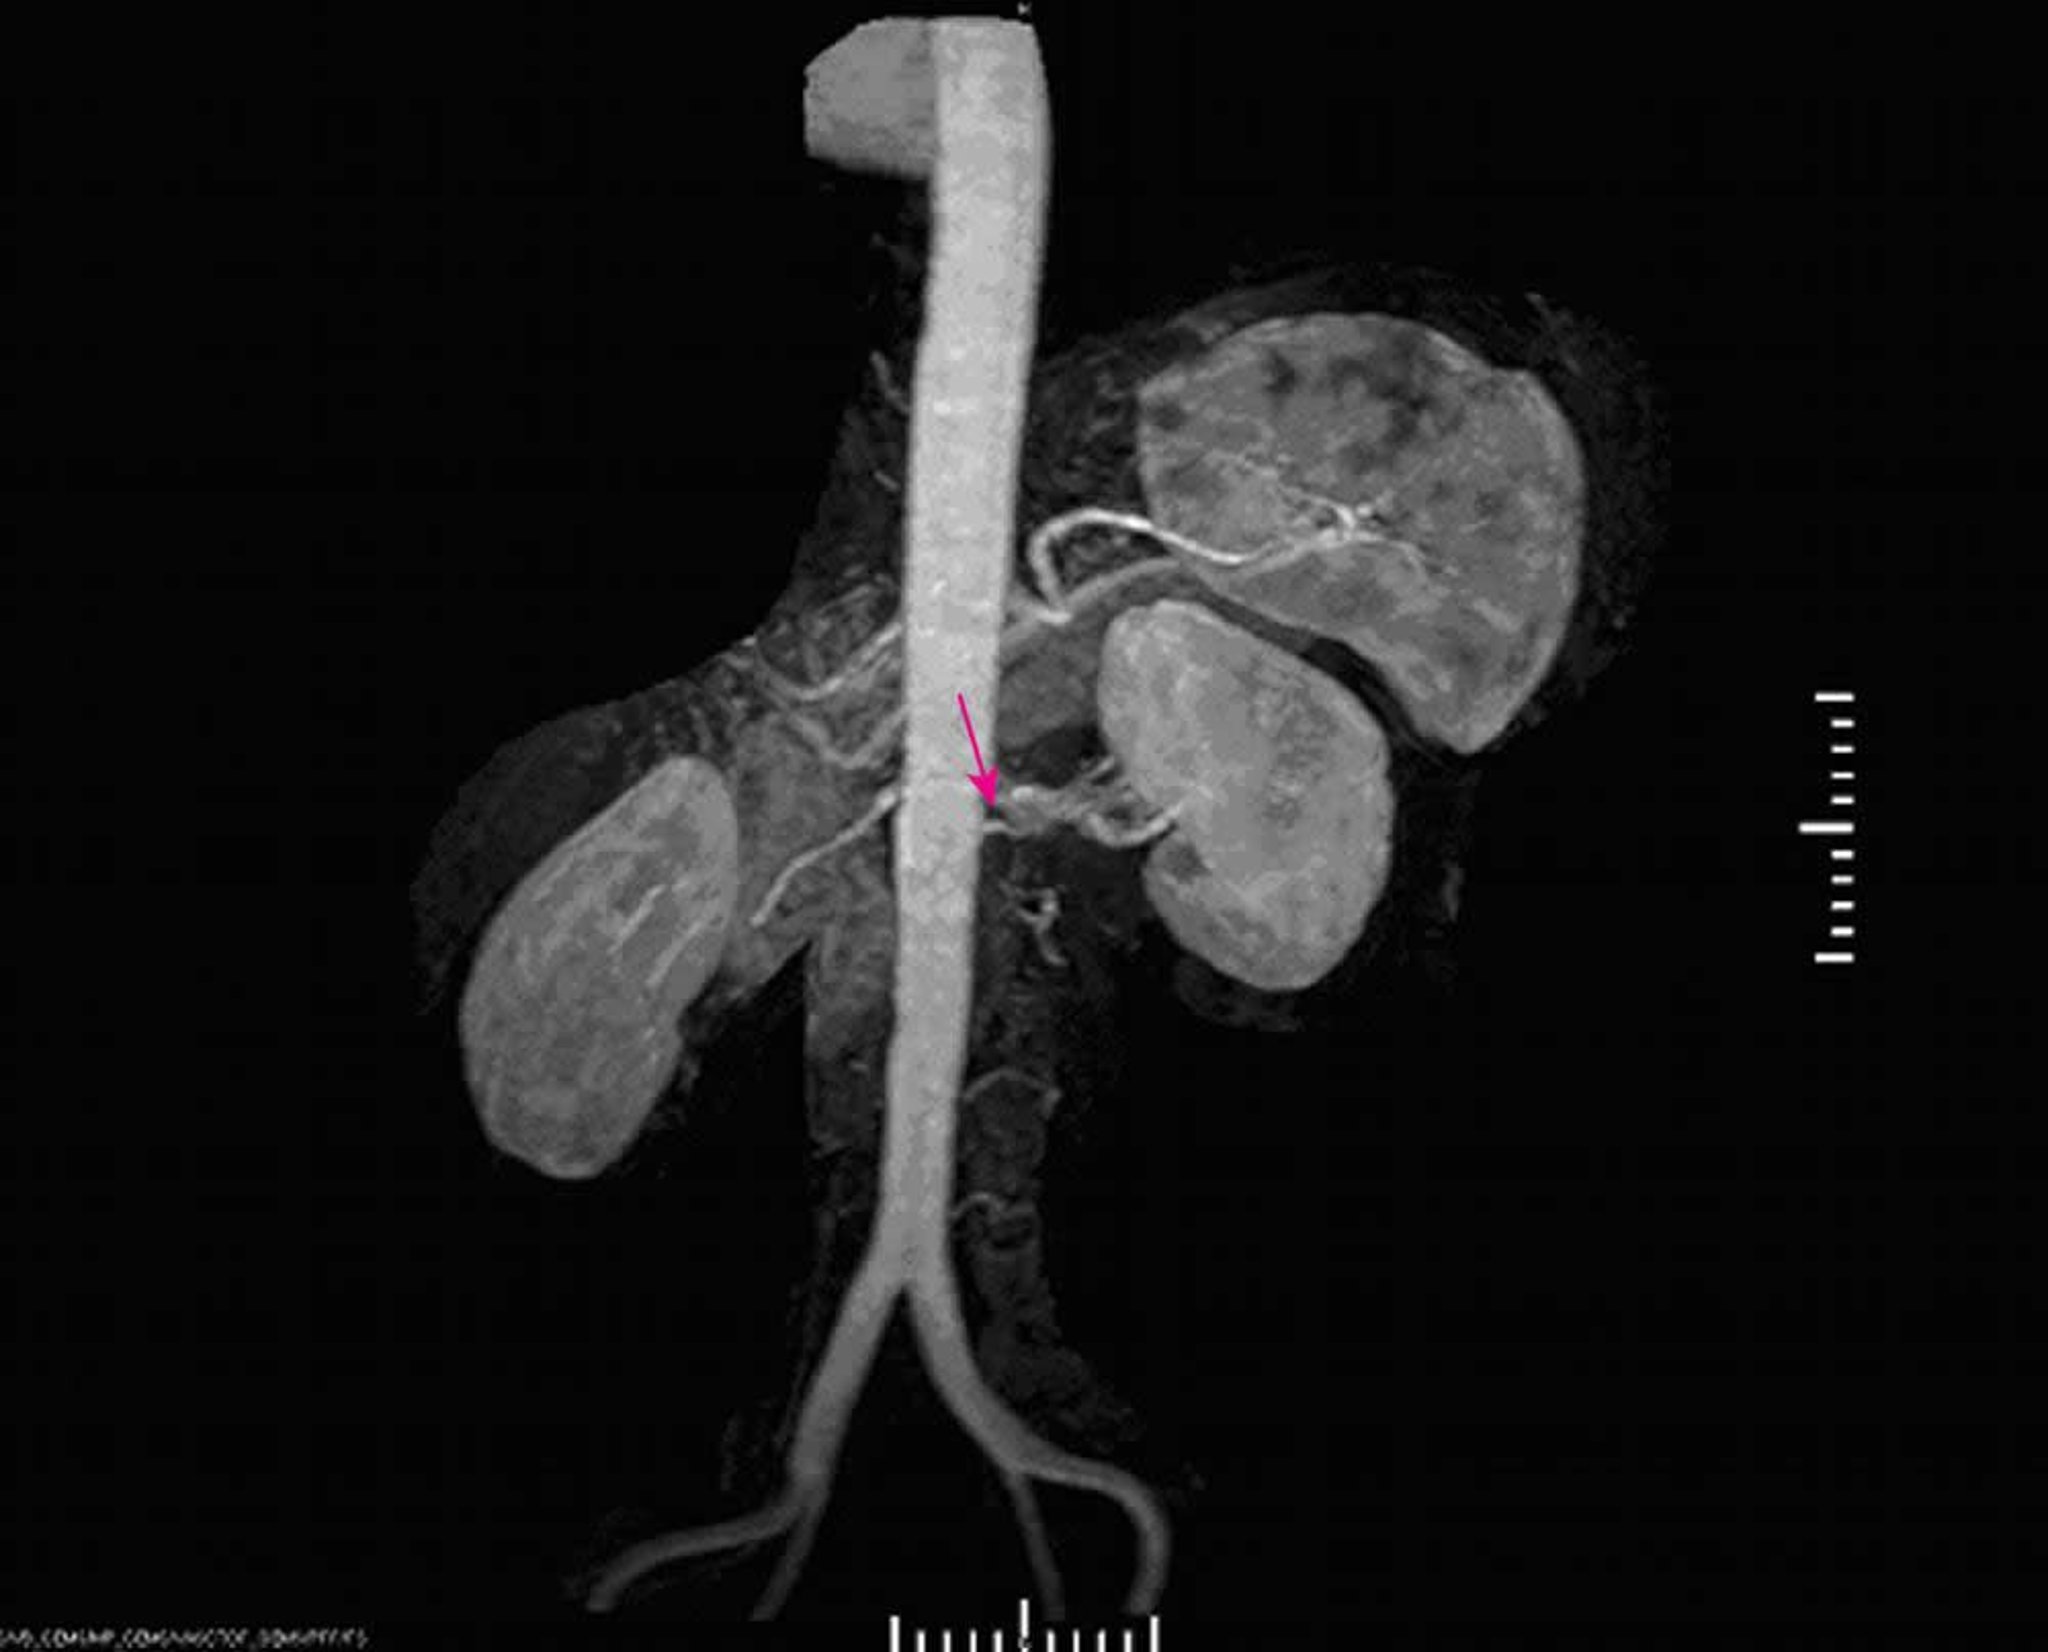

Реноваскулярная гипертензия (магнитно-резонансная ангиография)

Магнитно-резонансная ангиография демонстрирует тяжелый стеноз у корня левой главной почечной артерии.

Image provided by Jan N. Basile, MD.